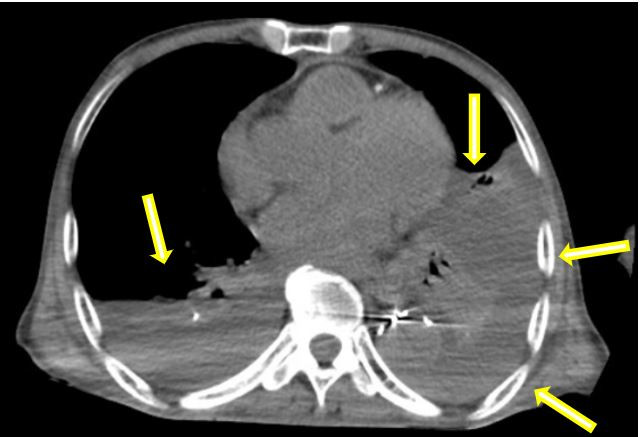

术后患者立即转入重症监护病房(ICU),在李红艳主任团队的精心管理下,患者一天后转回血管外科病房,患者生命体征稳定。根据术后CT复查结果,为解除肺部压迫、缓解呼吸困难,术后胸心外科陈阳天主任团队对患者进行了胸腔穿刺引流,双侧胸腔引流出2000多毫升的不凝血性液体,这几乎相当于人体一半的血容量。经过悉心的护理,患者术后恢复稳定,呼吸、心率及全身状况均得到了明显改善,各项生化指标平稳恢复,术后第十天,顺利康复出院。

术前:双侧胸腔大量积血,双肺受压(箭头示)

术后:经引流后胸腔大量积液消失,肺部压迫解除(箭头示)